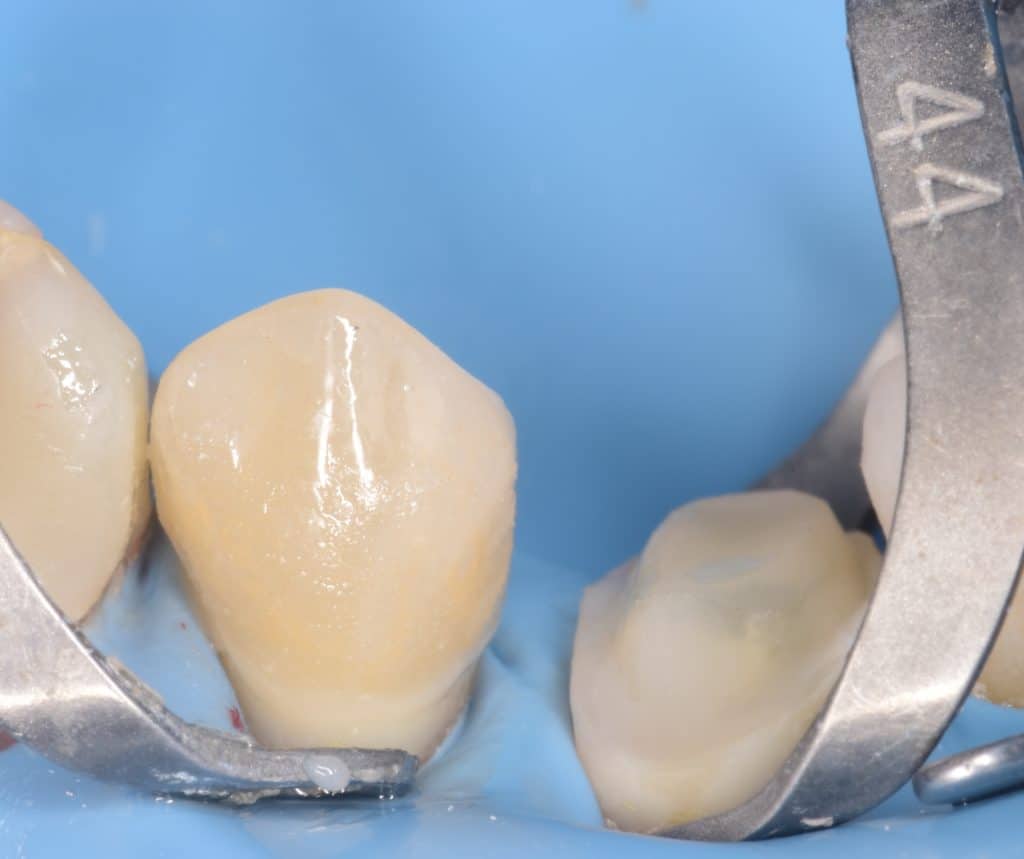

Preparation done , macro-core buildup for premolars

Cementation day, isolation with rubberdam, biobase air abraded

Buccal view showing the macro-core buildup